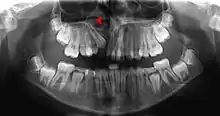

![]() Human jaws with anterior (frontal) portion of alveolar processes cut away towards right | |

On the maxilla, the alveolar process is a ridge on the inferior surface, making up the thickest part of the bone. On the mandible it is a ridge on the superior surface. The structures hold the teeth and are encased by gums as part of the oral cavity.[11] Either alveolar process comprises cells, nerves, blood vessels, lymphatic vessels, and periosteum.[8] The alveolar crest terminates uniformly at about the neck of the teeth (within about 1 to 2 mm in a healthy specimen).[12][13]

The alveolar process proper encases the tooth sockets, and contains a lining of compact bone around the roots of the teeth, called the lamina dura.[8] This is attached by the periodontal ligament (PDL) to the root cementum.[8] Although the alveolar process is composed of compact bone, it may be called the cribriform plate because it contains numerous holes where Volkmann's canals pass from the alveolar bone into the PDL. The alveolar bone proper is also called bundle bone because Sharpey's fibres, part of the PDL, are inserted there. Sharpey's fibres in alveolar bone proper are inserted at a right angle (just as with the cemental surface); they are fewer in number, but thicker in diameter than those found in cementum.[8]

The supporting alveolar bone consists of both cortical (compact) bone and trabecular bone. The cortical bone consists of plates on the facial and lingual surfaces of the alveolar bone. These cortical plates are usually about 1.5 to 3 mm thick over posterior teeth, but the thickness is highly variable around anterior teeth.[13] The trabecular bone consists of cancellous bone that is located between the alveolar bone proper and the cortical plates.[14]